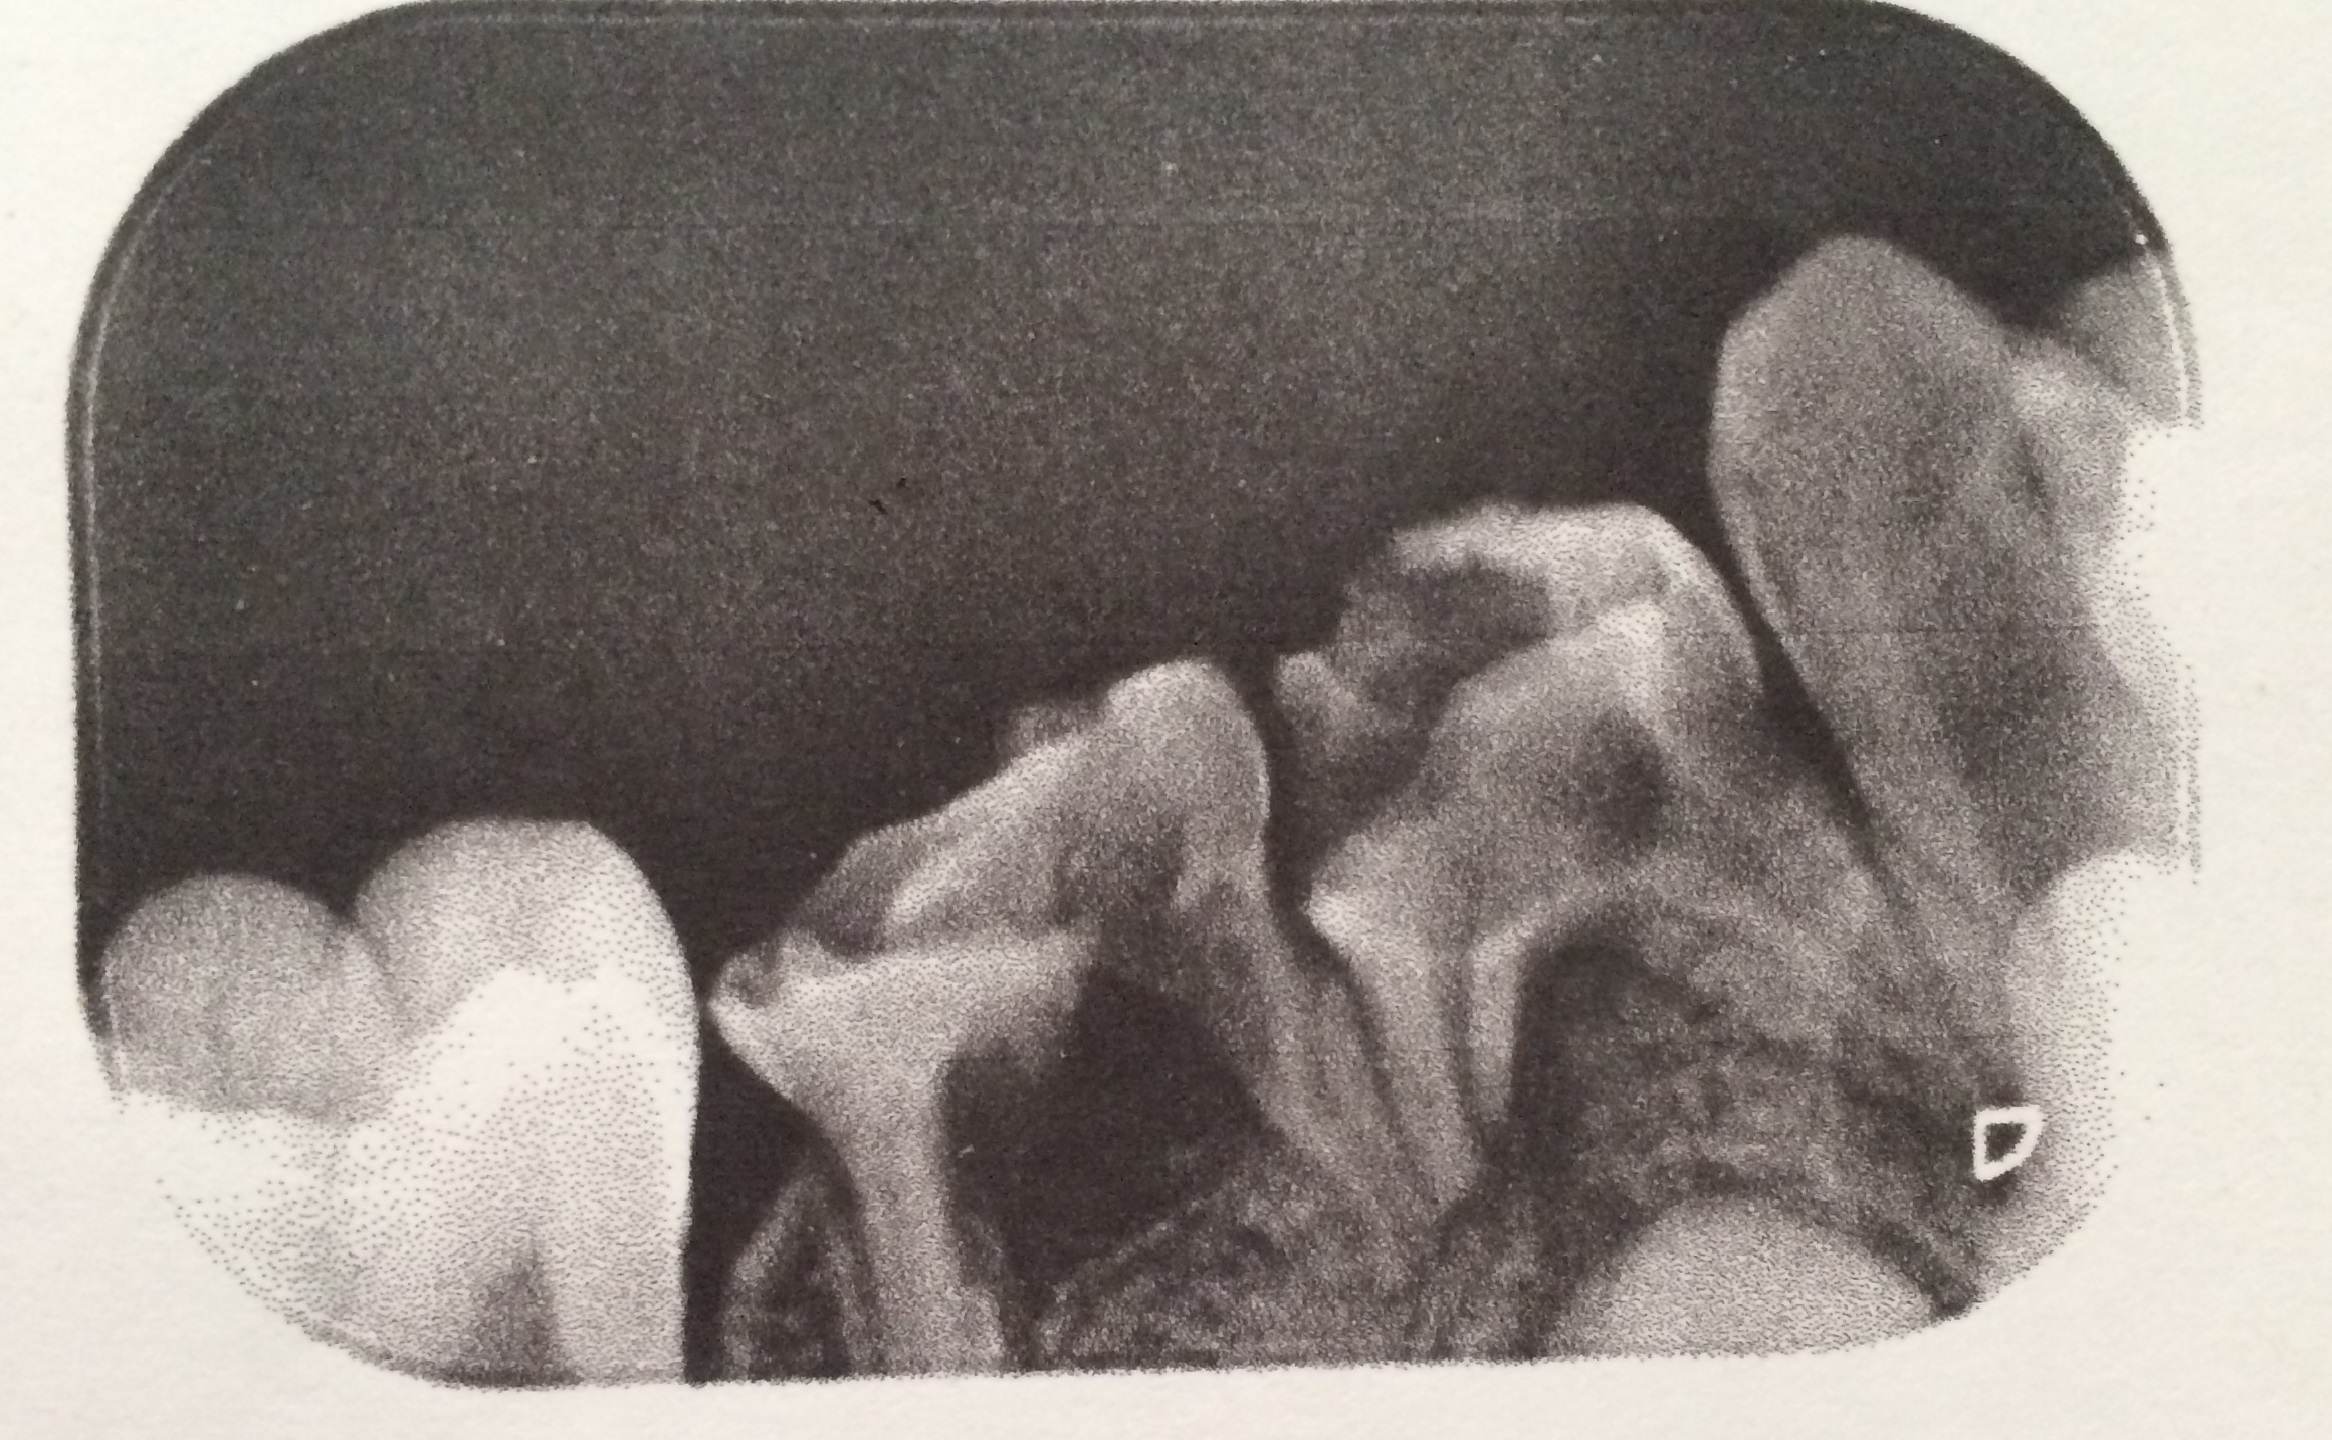

Perforasi iatrogenik merupakan salah satu resiko yang sering terjadi dalam perawatan endodontik yang disebabkan oleh kesalahan operator. Perforasi dapat terjadi pada apeks, lateral atau korona. Perawatan untuk perforasi dapat dilakukan dengan bedah atau non bedah. Prognosis dari perforasi endodonti dipengaruhi oleh beberapa faktor antara lain adalah waktu terjadinya perforasi, lokasi perforasi dan besarnya perforasi. Tujuan laporan kasus ini untuk melaporkan perawatan perforasi korona pada pulpektomi gigi decidui. Kasus seorang anak laki-laki usia 6 tahun datang bersama ibunya dengan keluhan gigi bawah belakang kanan sering sakit tiba-tiba sejak tiga bulan yang lalu. Diagnosis pada gigi molar pertama kanan rahang bawah adalah karies profunda kelas I dengan pulpitis irreversible. Perawatan yang dilakukan adalah pulpektomi. Dalam proses perawatan terjadi perforasi korona di mesial yang disebabkan oleh trauma bur preparasi saat dilakukan pembukaan atap pulpa. Perawatan pulpektomi tetap dilanjutkan dengan menutup daerah perforasi dengan zinc phosphat cement dan diakhiri dengan tumpatan tetap stainless steel crown (SSC). Kesimpulan dari laporan kasus ini yaitu perawatan perforasi korona dengan non bedah pada pulpektomi gigi decidui mempunyai prognosis yang baik. Perawatan dilakukan dengan bahan tumpatan yang memiliki ketahanan terhadap saliva dan tidak mengiritasi pulpa ataupun gingiva.